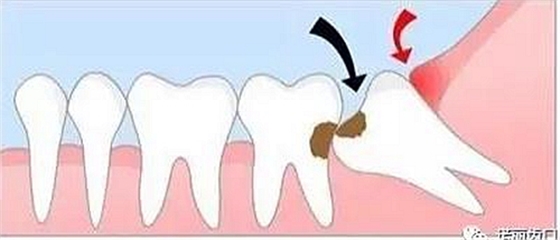

造成鄰牙病變

如果生長空間不足,智齒會使勁兒頂住相鄰的牙齒繼續(xù)生長,可能導致兩顆牙齒都保不住,此時建議拔除。